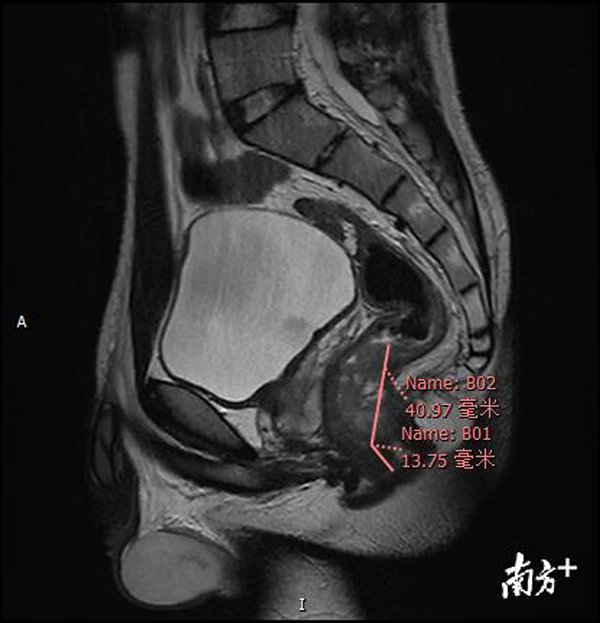

Sau khi hỏi tiền sử gia đình của bệnh nhân, bác sĩ Lian Lei ngay lập tức tiến hành kiểm tra hậu môn cho bệnh nhân và thấy rằng cạnh dưới của khối u cách mép hậu môn chưa đến 2cm. Với khối u thấp như vậy, bác sĩ thật sự phân vân không biết liệu có thể giữ lại được hậu môn cho chàng trai trẻ.

Sau khi thảo luận với bác sĩ chẩn đoán hình ảnh, bác sĩ Lian Lei phát hiện ra rằng khối u Xiaoqiang đã bị vỡ qua biểu mô 5-15mm, điều đó có nghĩa là khối u đã bước vào giai đoạn muộn. Nếu không được phẫu thuật kịp thời, khối u sẽ tiếp tục xâm lấn các mô xung quanh, điều này sẽ đe dọa nghiêm trọng đến cuộc sống của Xiaoqiang.